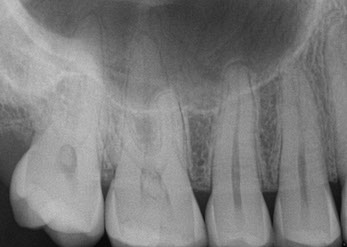

HD Digital X-ray Small Cavity